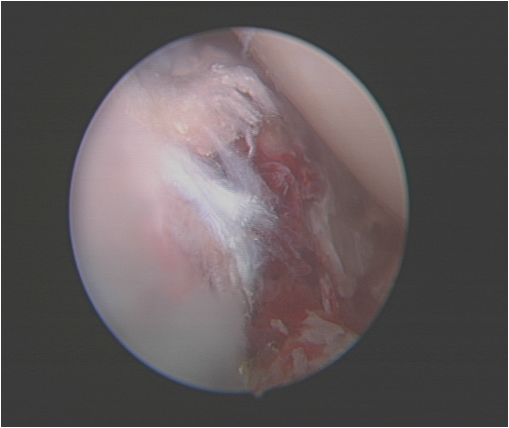

半月板缝合